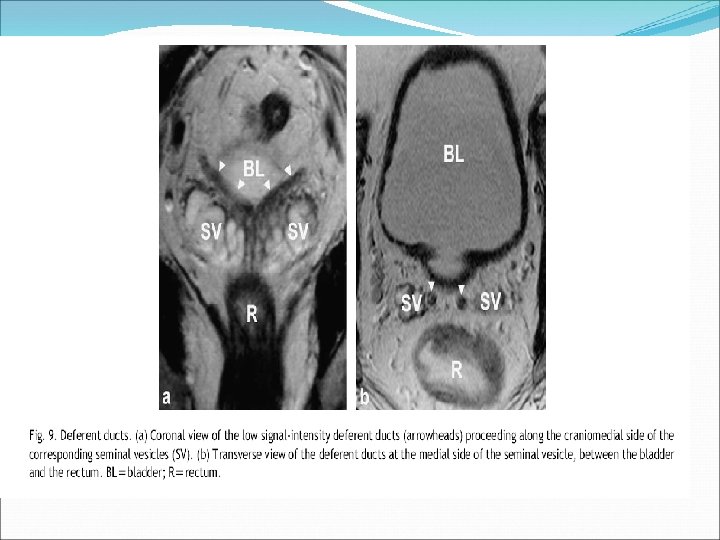

Seminal vesicles • located superior to the base of the prostate. • They undergo confluence with the vas deferens on each side to form the ejaculatory ducts. The ejaculatory duct complex consists of the two ejaculatory ducts along with a second loose stroma rich in vascular spaces. • The utricle (when present) is located between the ejaculatory ducts. The remnants of the utricle occasionally form cystic structures in the midline posteriorly. • The seminal vesicles are resistant to nearly all of the disease processes that affect the prostate. Seminal vesicle involvement (SVI) by prostate cancer (PCa) is one of the most important predictors for PCa progression